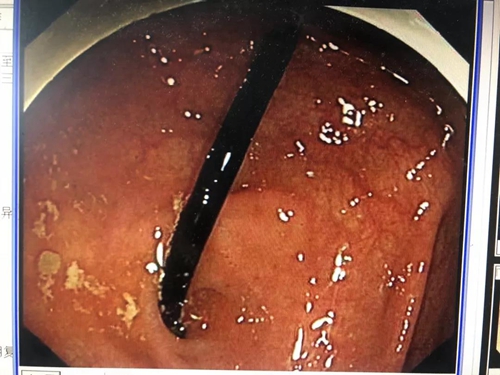

通过前期的肠道准备,5月14日,杨伟兴再次安排罗锋做了腹部CT检查,结果提示钉子已经滑落至回盲部。时机正好,杨伟兴立即准备为罗锋做急诊结肠镜检查。

10分钟后,杨伟兴从罗锋回盲部顺利取出一根35mm的钉子。而此时距离罗锋误吞钉子已过去了43个小时。